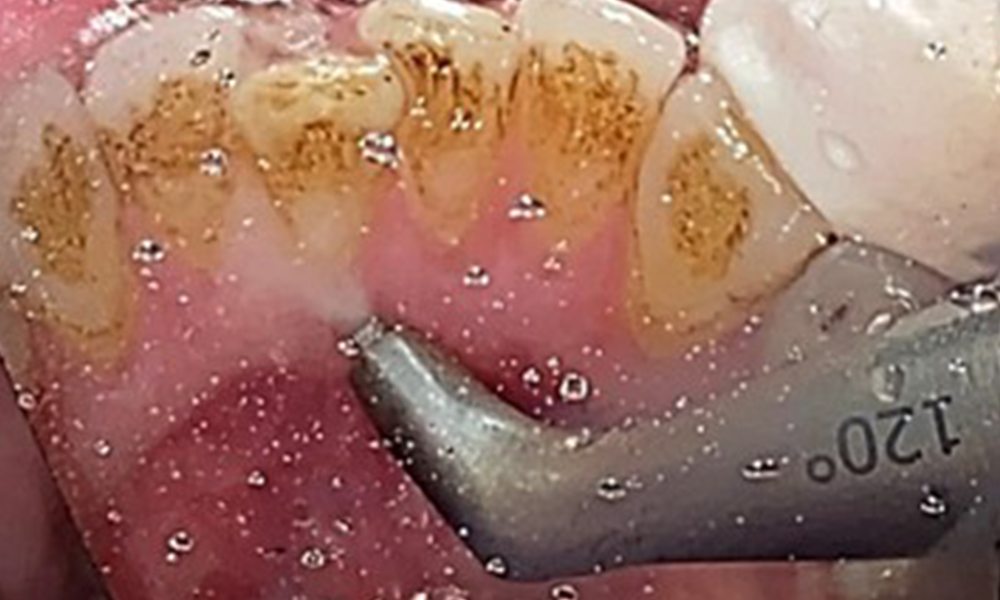

Taschensondierung (BOP) mit Darstellung der Rg. 36 lingual

Abb. 7 Taschensondierung (BOP) mit Darstellung der Rg. 36 lingual, © Dr. R. Krapf

Aufgrund des guten allgemeinmedizinischen Zustandes ist der aus der Mundgesundheit ermittelte Bedarf maßgebend für die Behandlung. Die regelmäßige Erhebung der Sondierungstiefen ist unabdingbar. Die gingivale Blutung ist bei Rauchern herabgesetzt, weswegen die klinische

Diagnose einer Parodontitis nur durch Sondierung möglich ist (Abb. 7). Die ausschließliche Erhebung von Blutungsindizes verdecken unter Umständen das Bild einer bestehenden Parodontitis oder Gingivitis. (5)